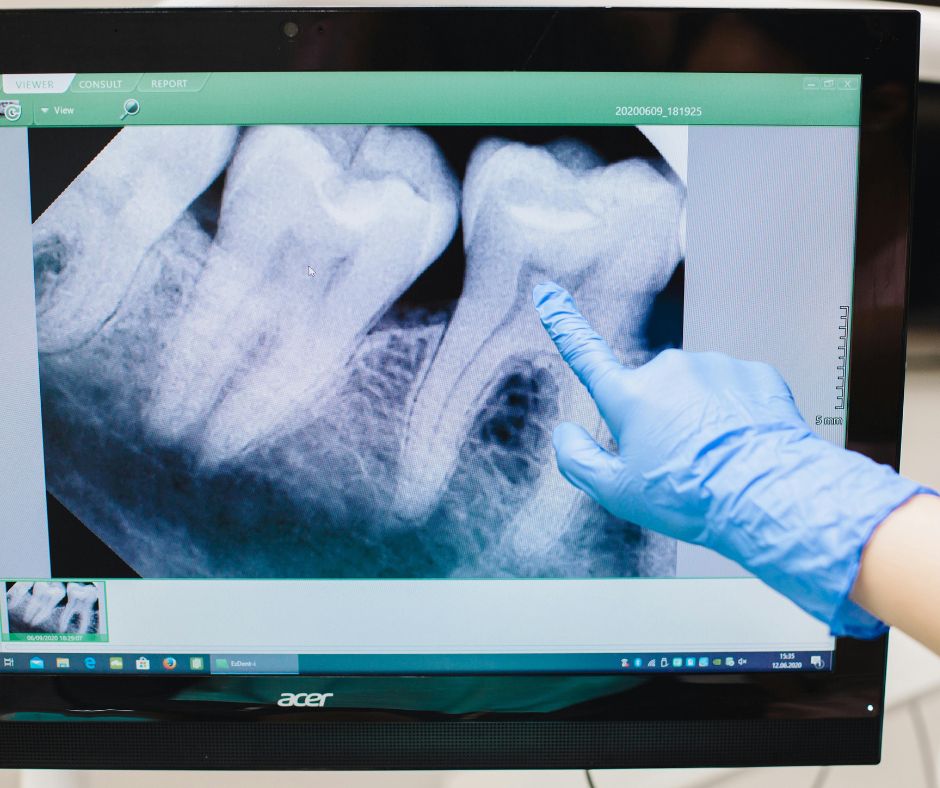

Wir nehmen uns Zeit für ein ausführliches Gespräch, analysieren Symptome, Vorerkrankungen und Belastungsfaktoren. Ergänzend nutzen wir bildgebende Verfahren wie digitale Volumentomographie (DVT) zur präzisen Lokalisierung potenzieller Herde.

• Modernste Technologie: 3D-Diagnostik mit DVT, metallfreie Versorgung, PRP zur Wundheilung